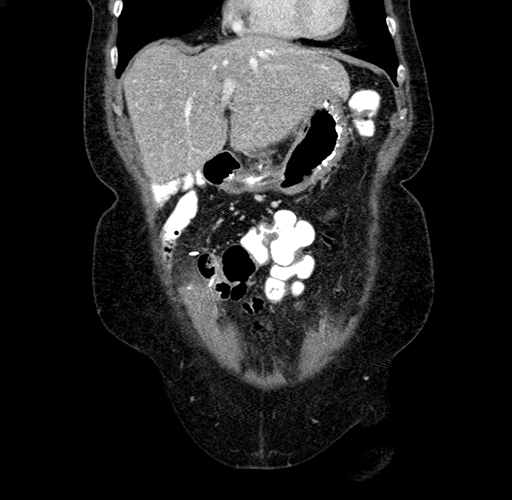

Coronal Venous